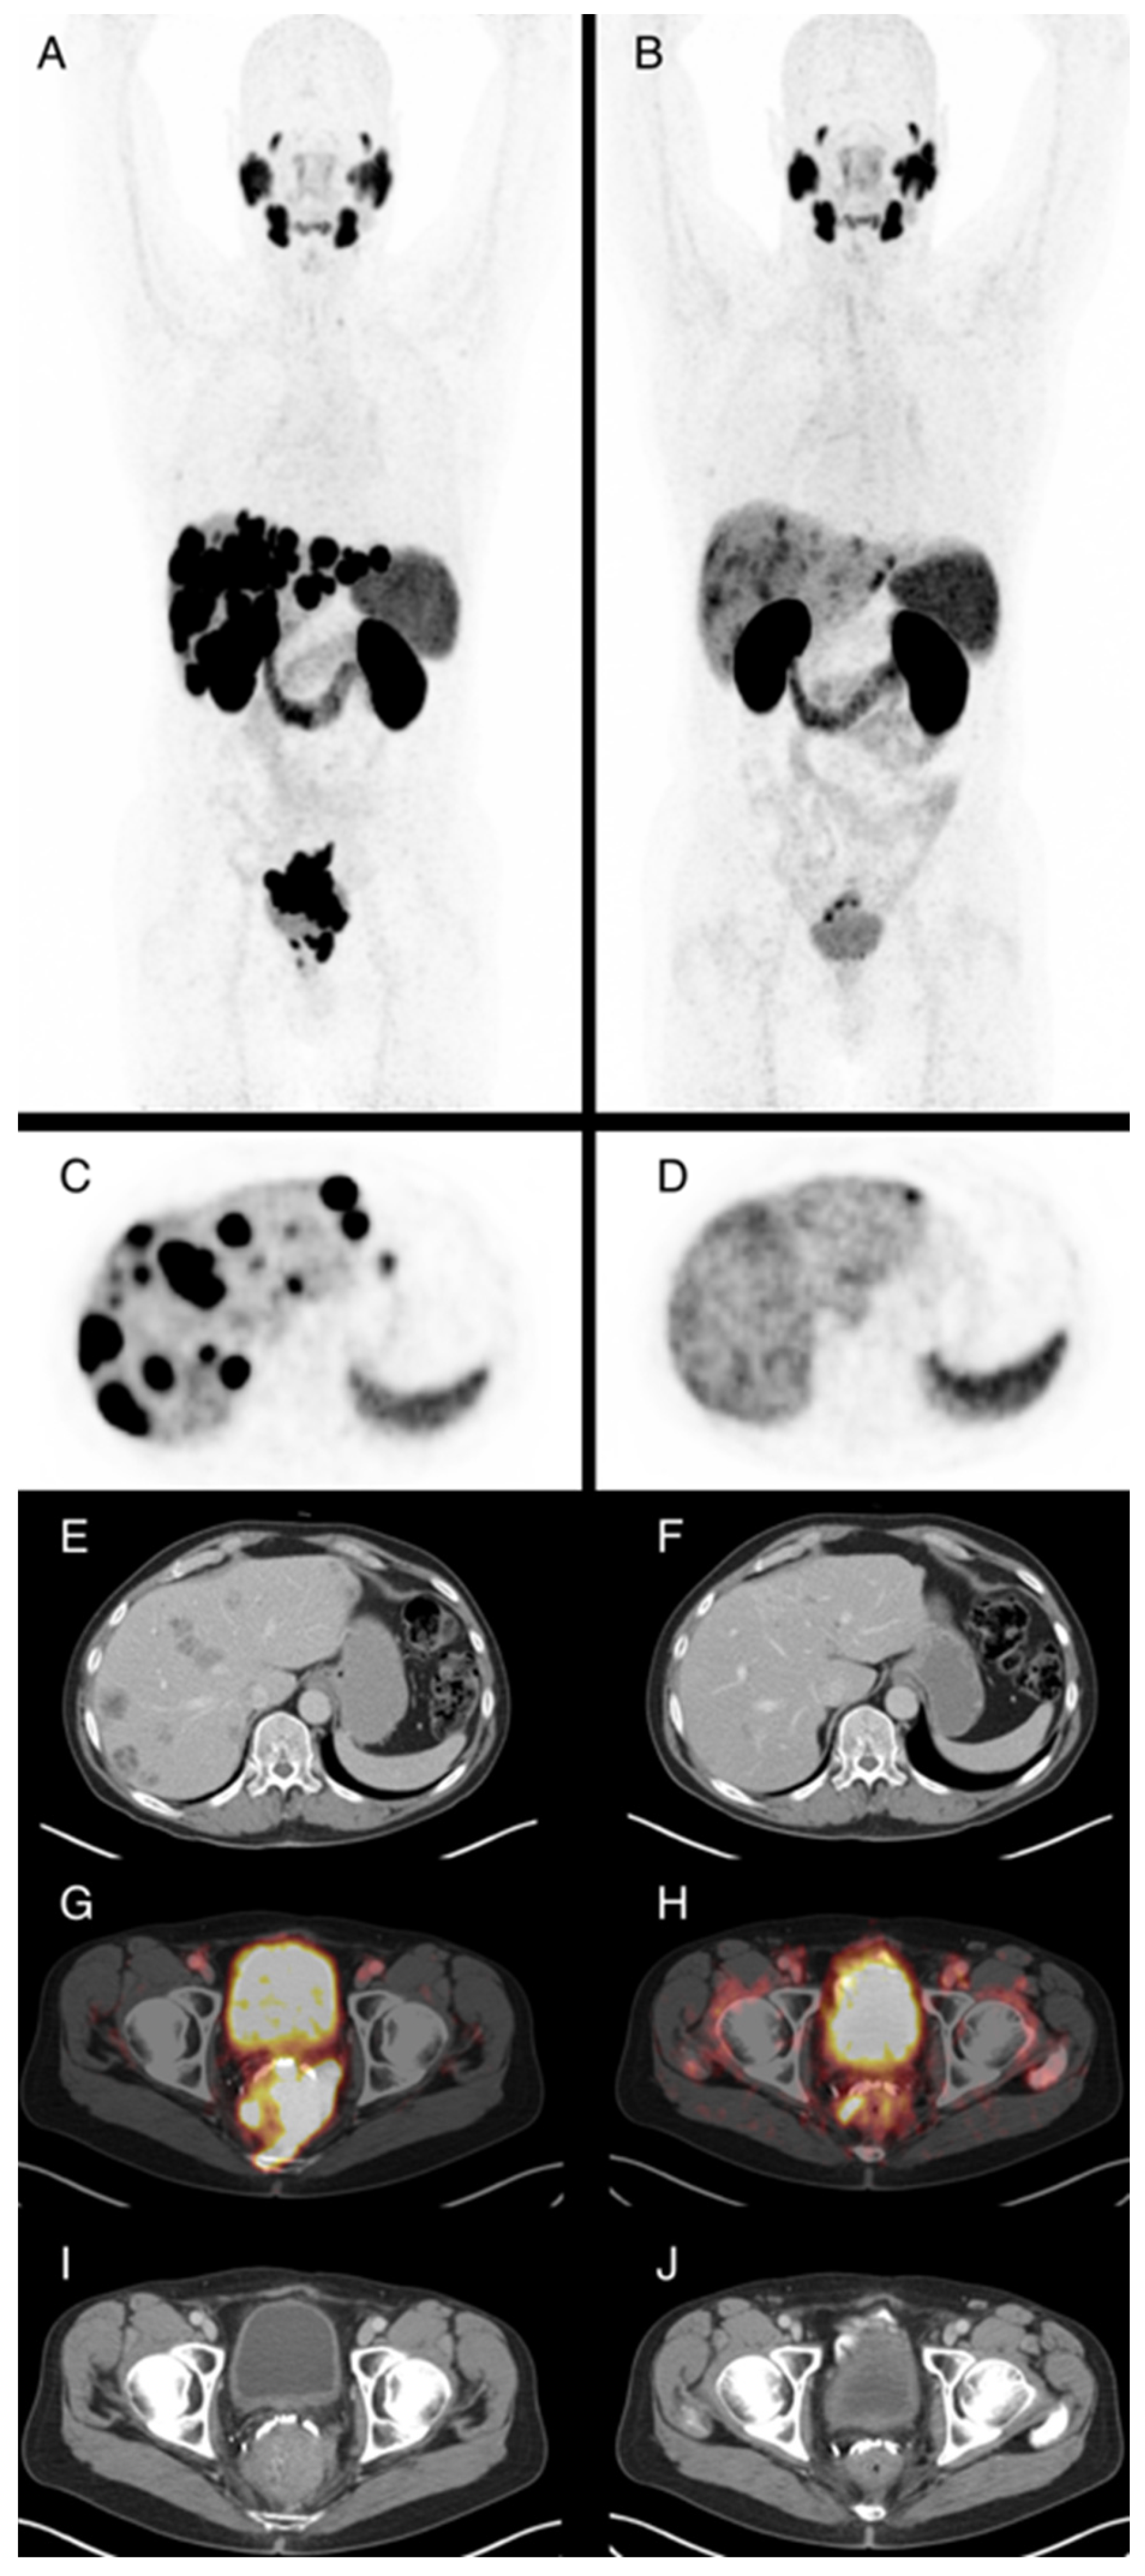

3.3. PSMA-PET/CT Response